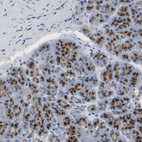

Immunohistochemical staining of human cerebral cortex, gastrointestinal, pancreas and prostate using Anti-TMEM87A antibody HPA018104 (A) shows similar protein distribution across tissues to independent antibody HPA018189 (B).